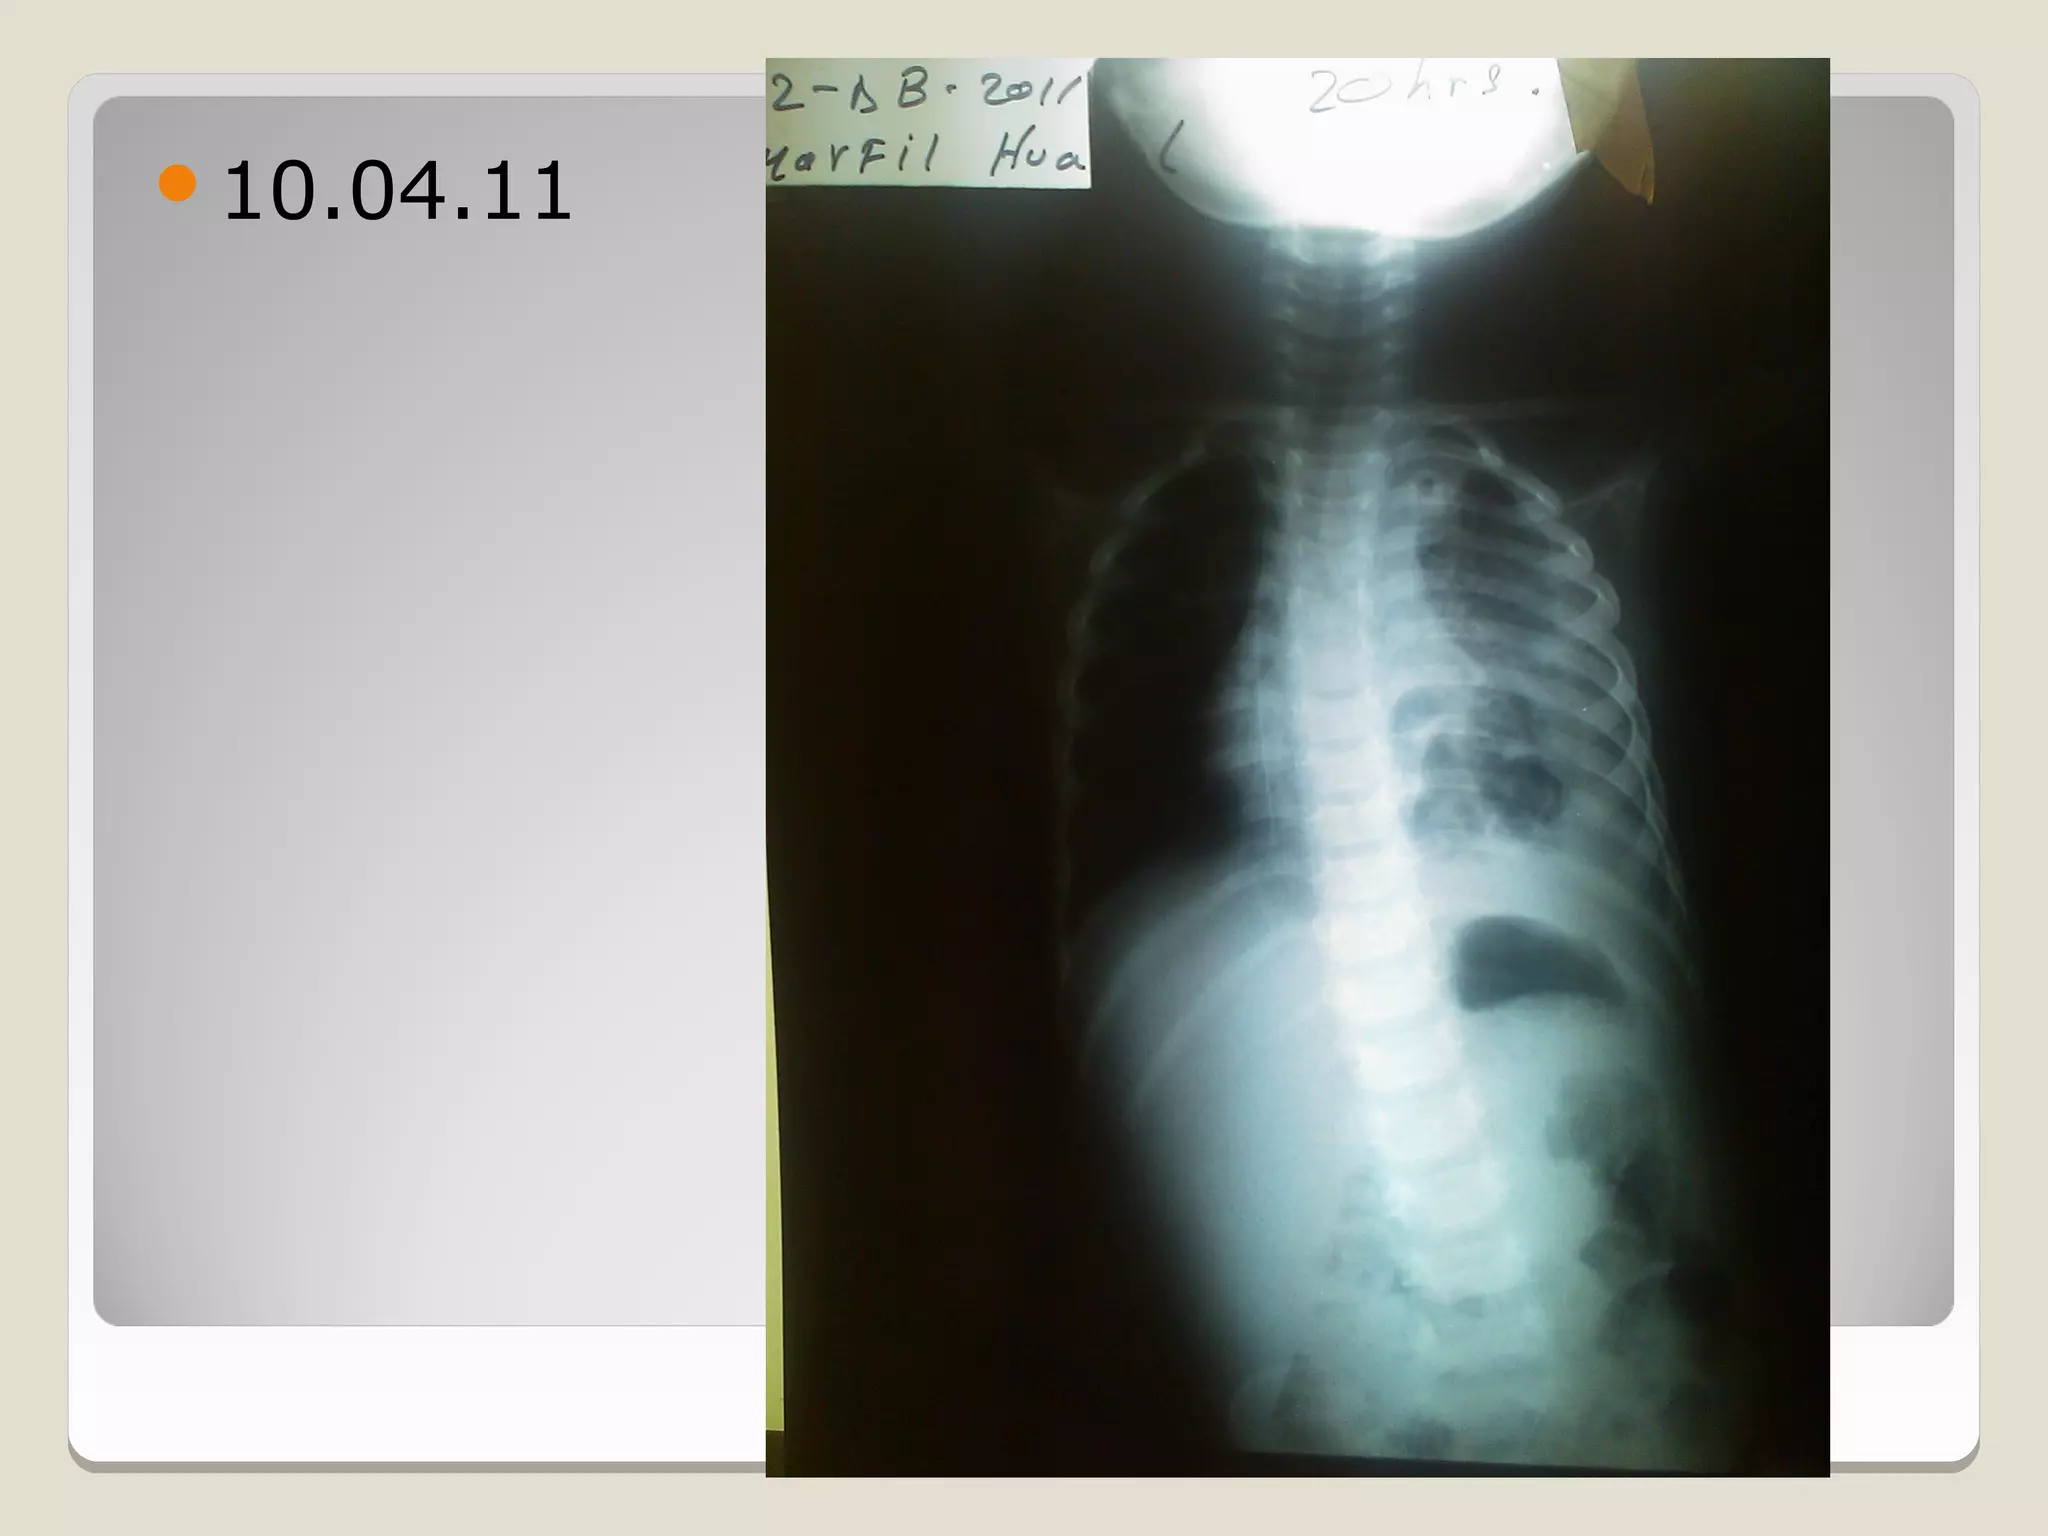

10.04.11